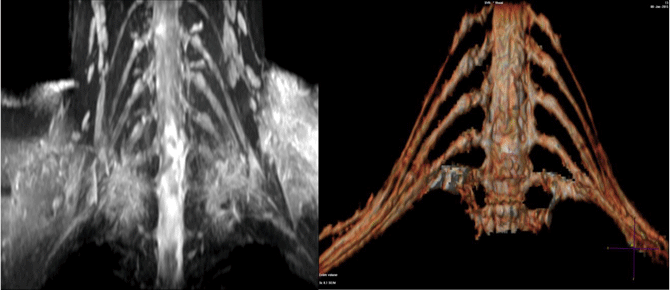

Chụp cộng hưởng từ đám rối thần kinh cánh tay giúp cho việc chẩn đoán và mô tả các tổn thương các bó sợi thần kinh, đặc biệt các tổn thương thứ phát của ung thư vú, phế quản. Các hội chứng từ lồng ngực, tổn thương đám rối sau chấn thương.

- Chụp chuỗi xung 3D Cube T2 Stir coronal, trường chụp phải bao phủ hết đám rối từ khớp vai bên phải đến khớp vai bên trái

- Hiện rõ mạng lưới thần kinh từ phần trước hạch đến phần sau hạch đến các nhánh tận